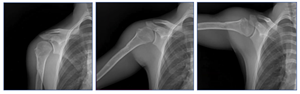

Dynamic Digital Radiography - Shoulder Series

DDR is a novel, low-dose X-ray imaging technique available on Konica Minolta Healthcare DR Systems that captures both static images and cinegrams, providing an innovative way to obtain detailed images of complex joints while in motion and observe physiological cycles.

DDR is a novel, low-dose X-ray imaging technique available on Konica Minolta Healthcare DR Systems that captures both static images and cinegrams, providing an innovative way to obtain detailed images of complex joints while in motion and observe physiological cycles. By acquiring a series of images at high speed, DDR generates a cineloop that enables clinicians to visualize anatomical motion over time (cineradiography), enhancing the system’s diagnostic capabilities. Studies have demonstrated the clinical utility of DDR in pulmonary medicine, orthopedics and other specialized applications such as swallow studies or post-bariatric sleeve assessments.